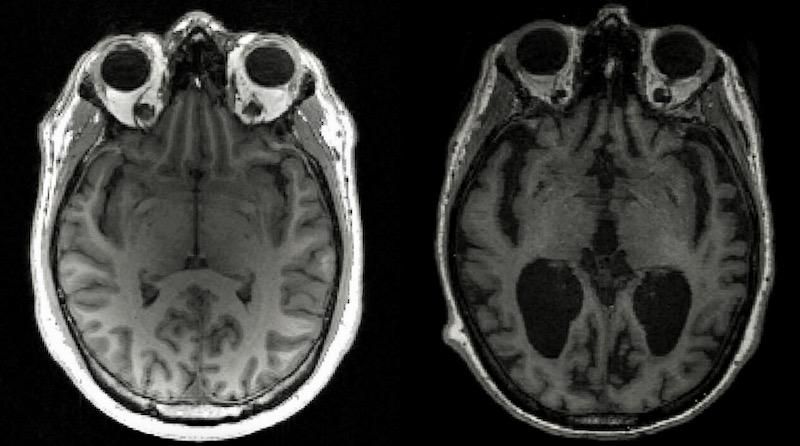

An MRI image of a healthy brain (L) and an Alzheimer's brain (R) with large black gaps where brain has shrunk Timothy Rittman University of Cambridge/AFP

In Alzheimer's disease, tau and another protein called amyloid-beta build up into tangles and plaques -- known together as aggregates -- that cause brain cells to die and lead to brain shrinkage.

This in turn results in memory loss, personality changes and inability to carry out daily functions associated with the condition, which affects 44 million people globally.